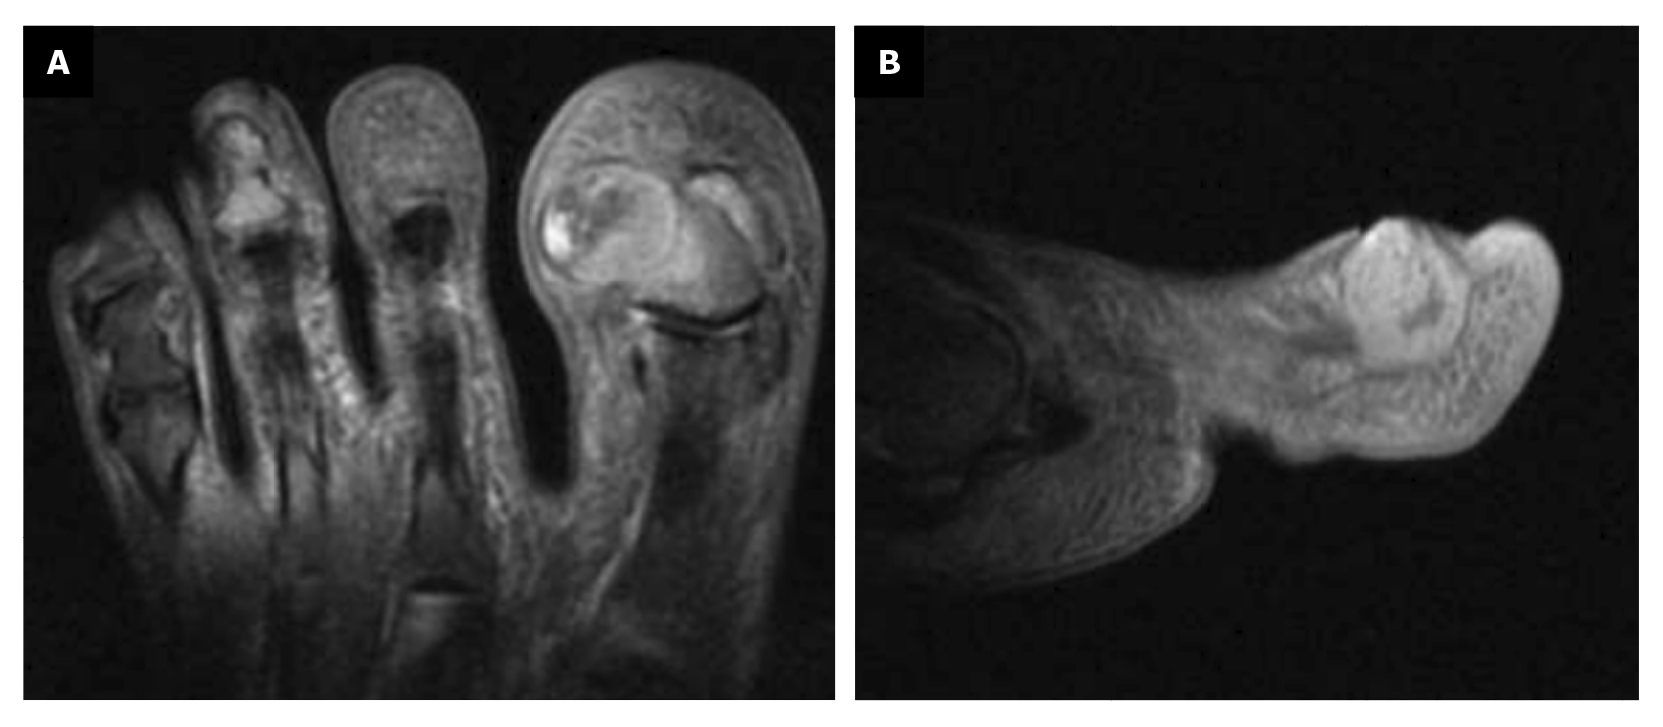

Within 3 weeks after the third intervention, the patient reported recurrence of the lesion and painful symptoms (Figure 7). The patient decided to attend the traumatology department (February 2023) where an MRI (T2FS and DPFATSAT) was requested. It showed an occupying mass in the lateral third of the first toe with well-defined borders and bone involvement (Figure 8) with the following report: “At the level of the distal phalanx of the 1st toe in the nail region, there appears to be a solution of skin continuity with a heterogeneous, a dense 15 mm x 14 mm collection in the lateral region of the parapharyngeal soft tissues, remodeling the bone and coming into contact with the flexor tendon, which could be consistent with a postoperative abscess/phlegmonous collection. Some bone edema in the distal phalanx is suspected, without completely ruling out incipient osteomyelitis. To be correlated with medical history and surgical protocol performed.”

Figure 8. Space ocuping mass with bone involvement. A: transverse plane; B: saggital plane.